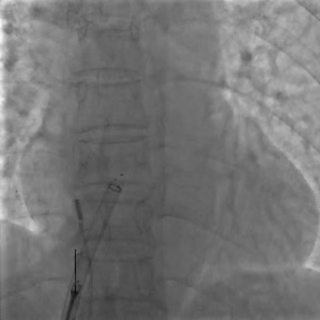

左盘展开

DSA下左盘展开,轻轻牵拉成型线辅助左盘成型,左盘1个Mark点靠近腰部2个Mark点

后撤钢缆和鞘管使左盘贴靠房间隔